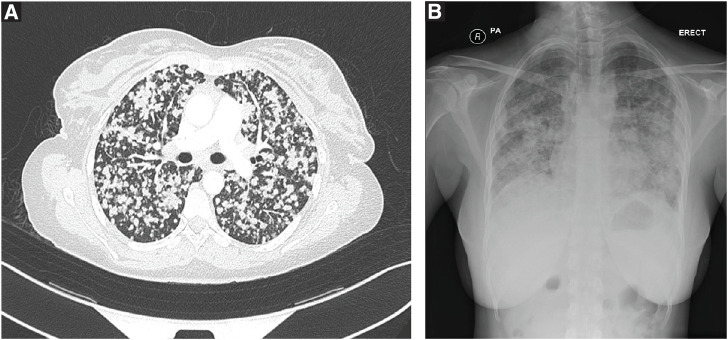

Case presentation: A 30-year-old female presented with respiratory symptoms and systemic complaints, initially suggestive of miliary TB. Further investigations revealed metastatic lung adenocarcinoma with pituitary metastasis, causing diabetes insipidus, hyperprolactinemia, adrenal insufficiency, and hypothyroidism. Treatment with targeted therapy involving osimertinib resulted in clinical improvement.